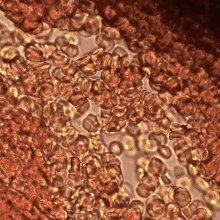

Erythrocytes aggregate in a special way, forming rouleaux. Rouleaux are stacks of erythrocytes which form because of the unique discoid shape of the cells in vertebrate body. The flat surface of the discoid RBCs give them a large surface area to make contact and stick to each other; thus, forming a rouleau. Rouleaux formation takes place only in suspensions of RBC containing high-molecular, fibrilar proteins or polymers in the suspending medium (often Dextran-2000 in-vitro). The most important protein causing rouleaux formation in plasma is fibrinogen. RBC suspended in simple salt solutions do not form rouleaux.[1][2][3]

Current experimental and theoretical evidence supports the mechanism related to the depletion of high-molecular weight molecules (e.g., fibrinogen) for rouleaux formation.[4] This mechanism is also known as “chemiosmotic hypothesis” for aggregation.[5] Erythrocyte aggregation is determined by both suspending phase (blood plasma) and cellular properties. Surface properties of erythrocytes, such as surface charge density strongly influence the extent and time course of aggregation.